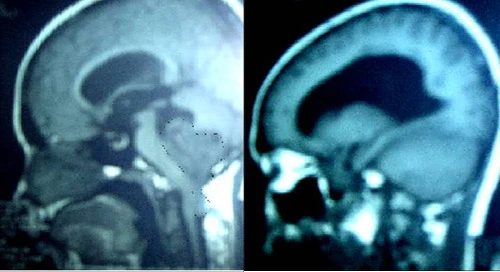

Đau đầu kéo dài nhiều tuần, bé gái 9 tuổi được phát hiện có khối u não lớn

Mổ lấy khối u não lớn để cứu thai phụ 22 tuần tuổi mà vẫn giữ được thai